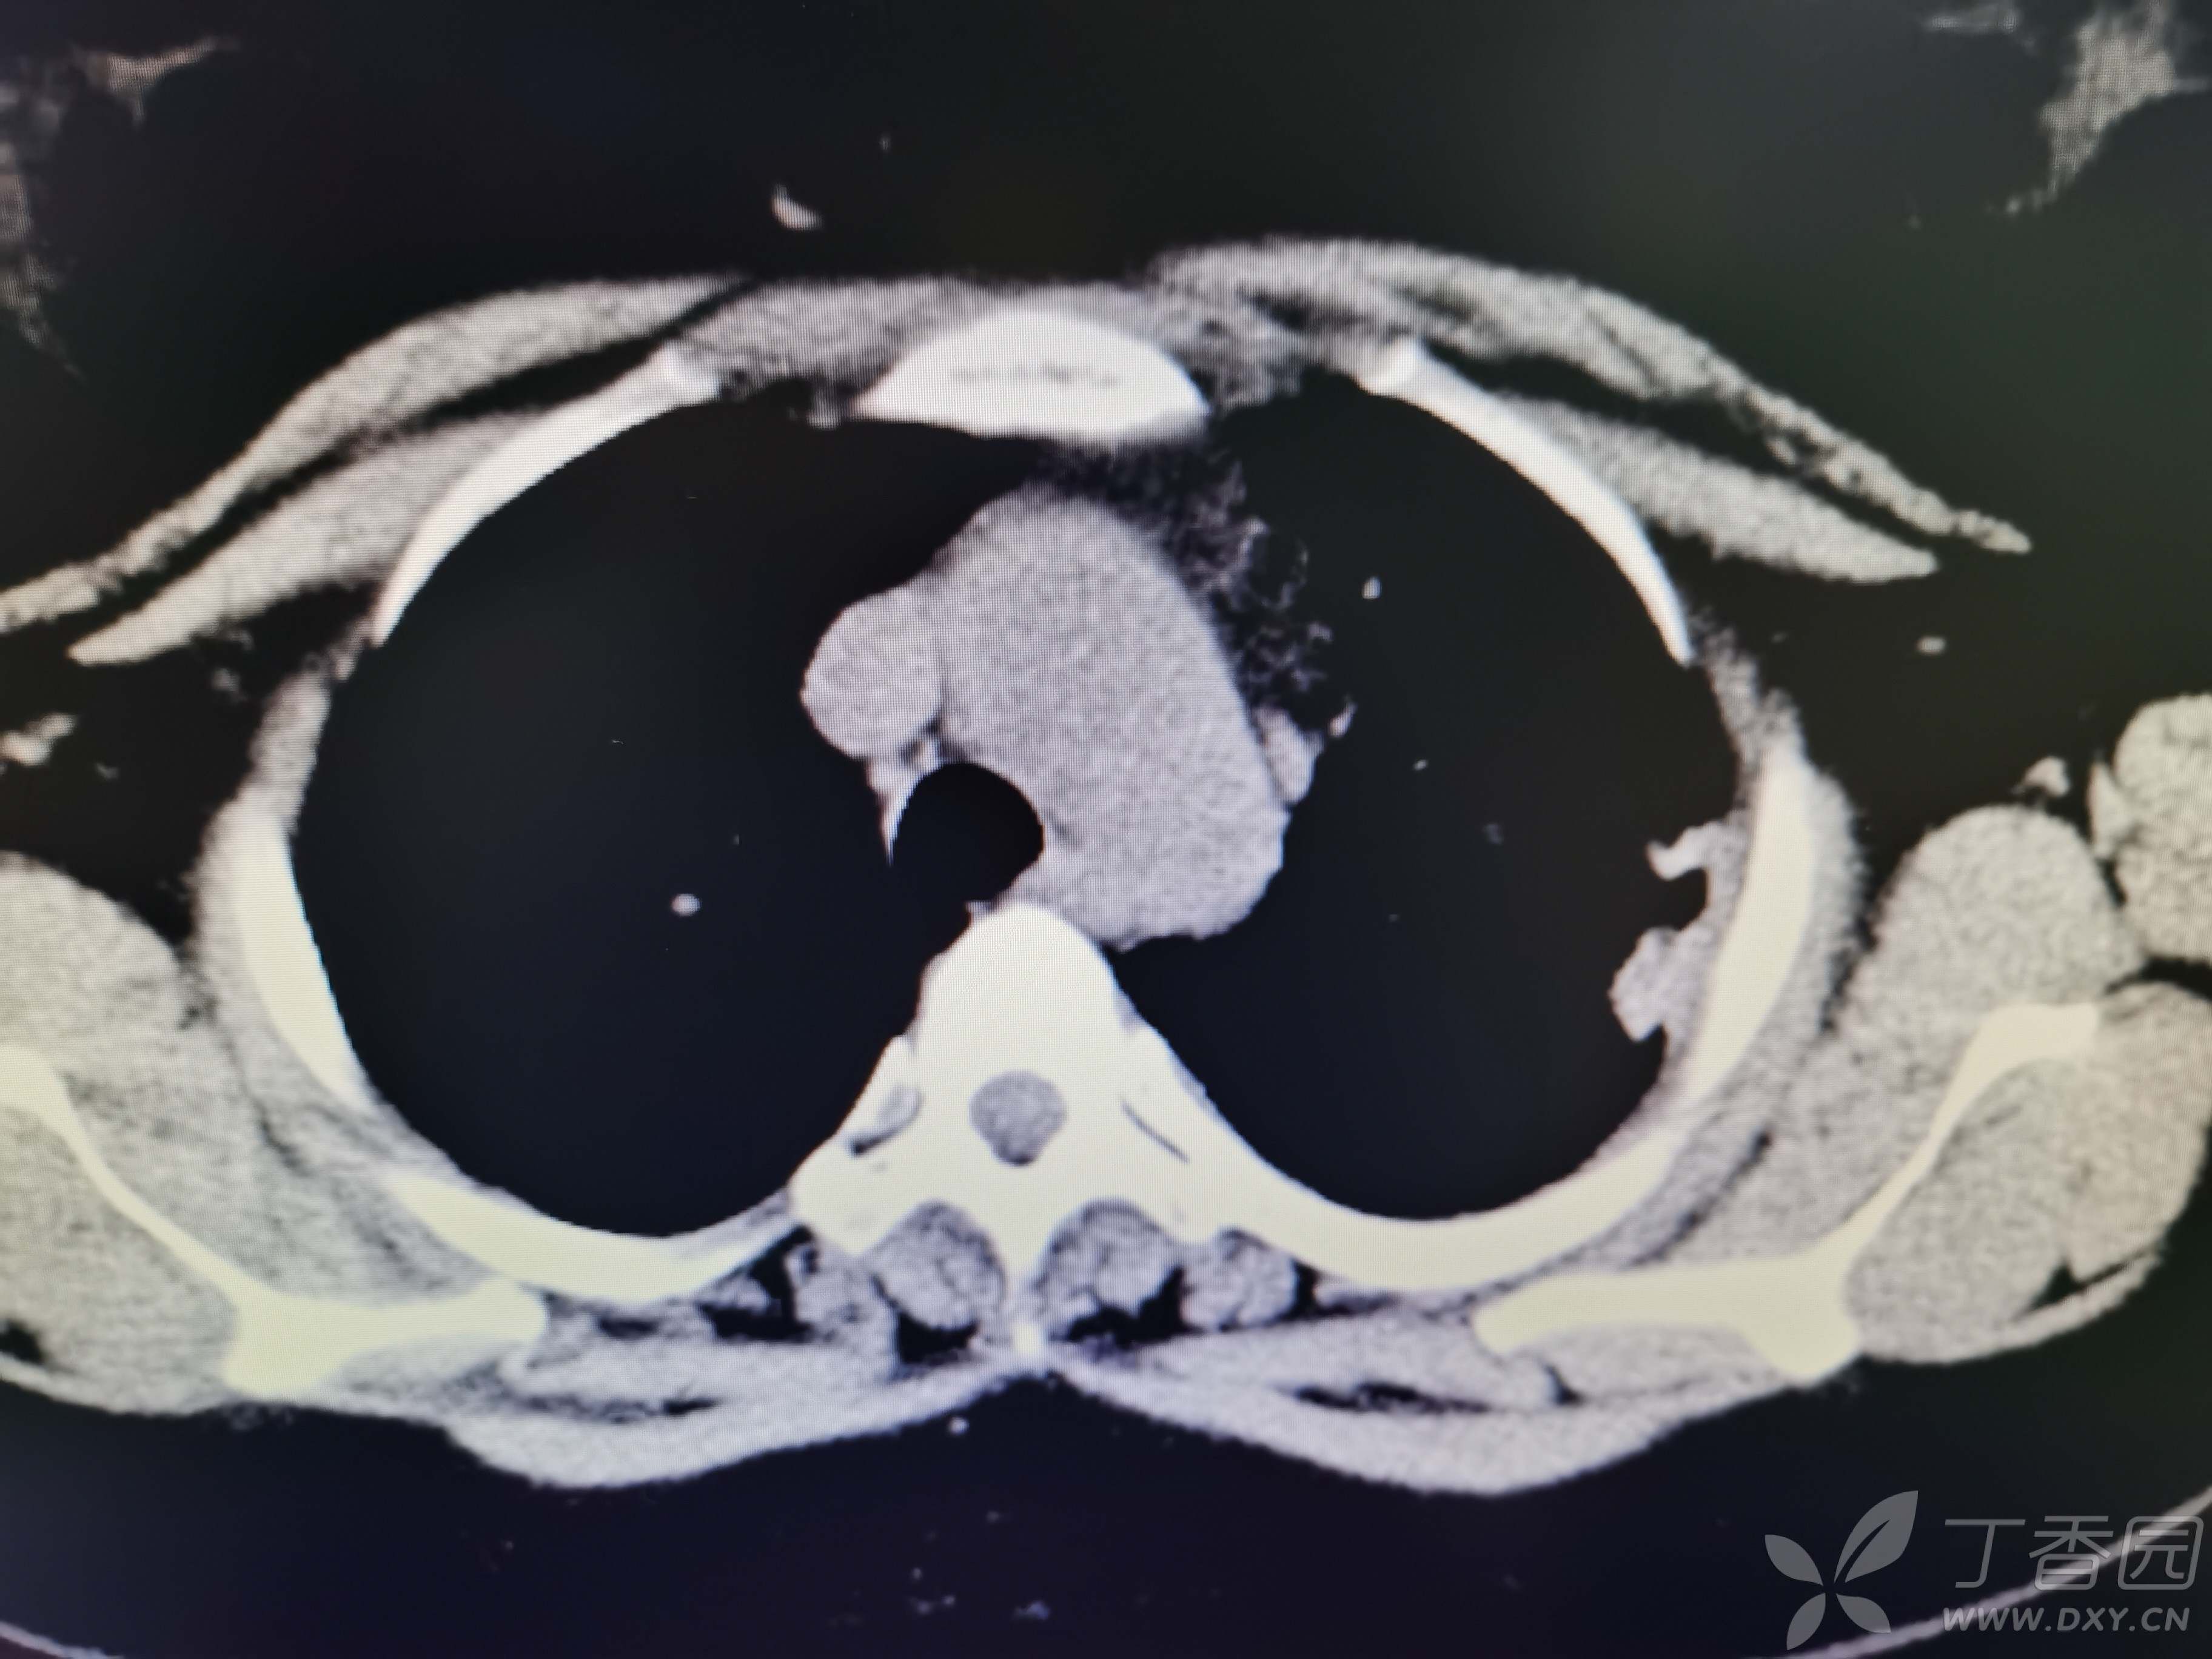

基本信息:女,三十几岁,印度人。。

胸部CT:

如题:猜肺部病灶病理。。